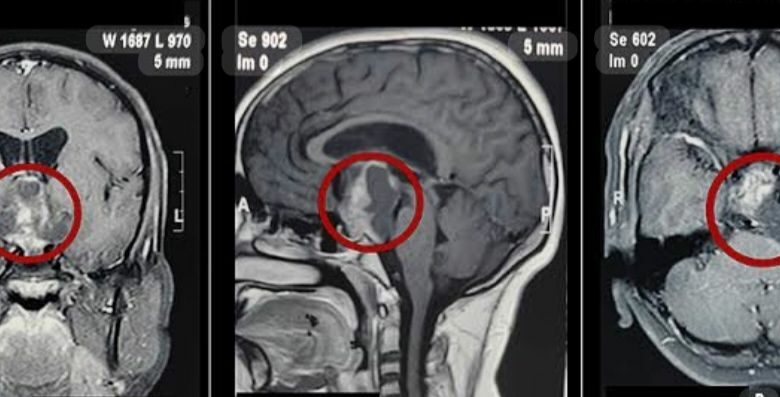

عملنا له CT Brain أشعة مقطعية على المخ، وتفاجأنا إن الأشعة سليمة، بس برضو العيان نايم ومش بيفوق.

في الآخر السينيور بتاعنا د/ عمر جابر، واستشاري العناية د/ أحمد العربي، قرروا يعملوا MRI (رنين مغناطيسي).

وهنا كانت المفاجأة، العيان عنده hypothalamic infarction، جزء في المخ ميت،

ويصادف أن الجزء اللي ميت في sleeping center مراكز النوم.

وده معناه إن العيان ده هيفضل نايم طول عمره مش هيصحى، ودي حالة نادرة جدًا.